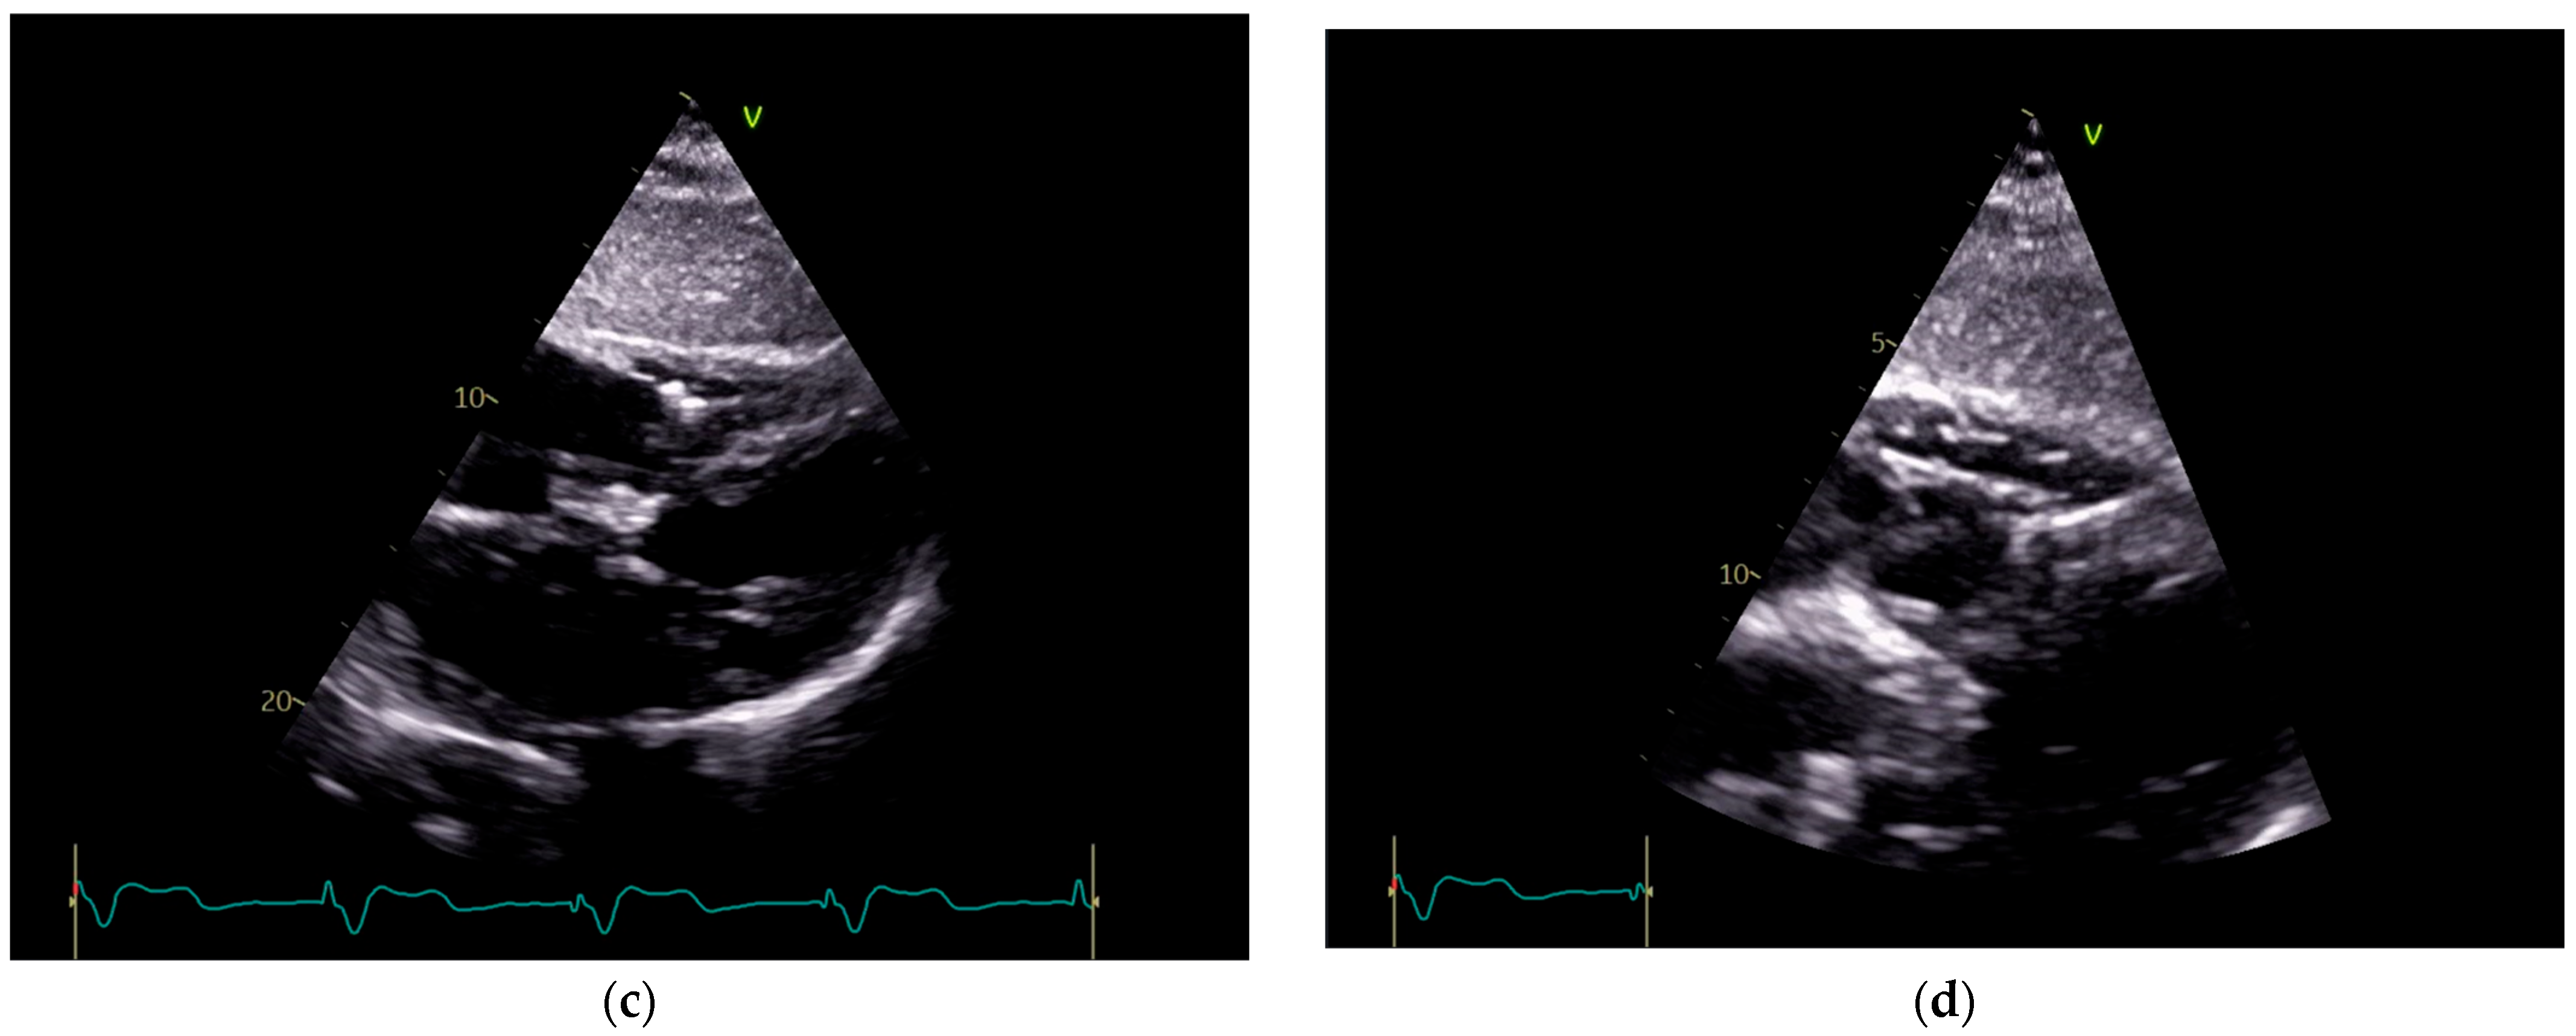

To investigate a potential cause of malfunction of the intracardiac device, it was decided that both a chest X-ray (Figure 2) and an echocardiogram (Figure 3) would be performed. These diagnostic tests were selected to confirm or rule out the possibility of a pacing probe fracture, particularly considering the patient’s recent fall, which may have compromised the integrity of the device or the intracardiac pacing leads. The chest X-ray assesses the device positioning and identifies potential fractures of the pacing leads. Concurrently, the echocardiogram provides critical information regarding cardiac function and its interaction with the implanted device. Together, these diagnostic modalities are essential for optimal management of the patient.

Figure 3. Echocardiography exam images at admission: A transthoracic echocardiography (TTE) exam was performed in the apical 4-chamber view (a,b) and subcostal view (c,d), revealing the insertion of the pacing probe into the myocardium of the right ventricle free wall, without any visible fractures or ruptures of the lead.

Figure 7. Holter ECG strip: The ventricular stimulated rhythm has a rate of 70 bpm. The pacemaker-generated spike is followed by a wide QRS complex. The lead is placed at the apex of the right ventricle (see Figure 3 and Figure 13C), depolarizing the right ventricle before the left ventricle. The lead is in contact with the myocardium, and the conduction is slow, cell-to-cell, thus generating a broad QRS, reflecting the interventricular and intraventricular dyssynchrony.